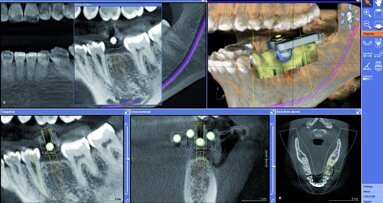

La chirurgie guidée existe depuis longtemps et pourtant, au Royaume-Uni, très peu de chirurgiens-dentistes posent des implants en se servant ...

ECKBOLSHEIM, France : La chirurgie implantaire continue d’évoluer avec l’intégration de solutions de plus en plus connectées. Dans ce contexte, les ...